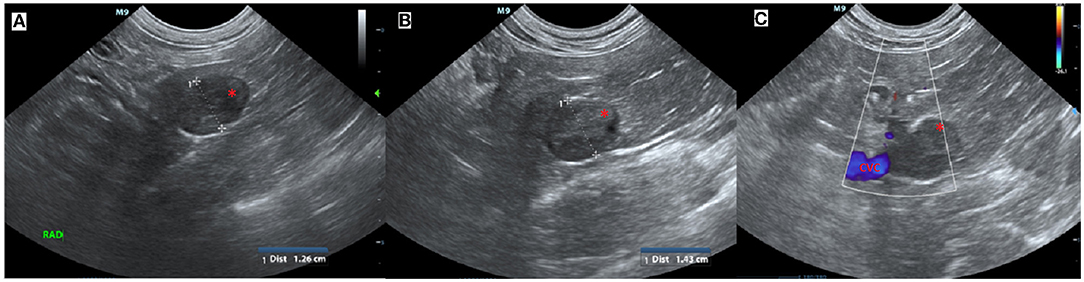

An 11-year-old female serval (Leptailurus serval) from Wellington Zoo was presented for a right adrenal mass, which had been progressively enlarging over the previous several months. The mass was initially found incidentally on abdominal ultrasound approximately 2 years previously while undergoing evaluation following a foreign body small intestinal obstruction (wood chip mulch). At initial diagnosis, the right adrenal gland was measured as 1.26 cm in comparison to the left adrenal gland, which measured 0.5 cm (Figure 1).

Figure 1. Ultrasound images of the right adrenal mass. (A) Initial ultrasound scan showing enlargement of the right adrenal gland (*). (B) A subsequent ultrasound scan approximately 11 months later showed progressive enlargement (calipers) of the right adrenal gland (*) and (C) in close association with the caudal vena cava (CVC, blue) but no evidence of invasion.

Successive abdominal ultrasounds indicated that the adrenal mass was expanding without evidence of invasion into the surrounding caudal vena cava or renal vasculature. The mass was encroaching on the right phrenicoabdominal vein but invasion into the vein could not be determined using ultrasound, and computed tomographic evaluation was recommended (Figure 1).